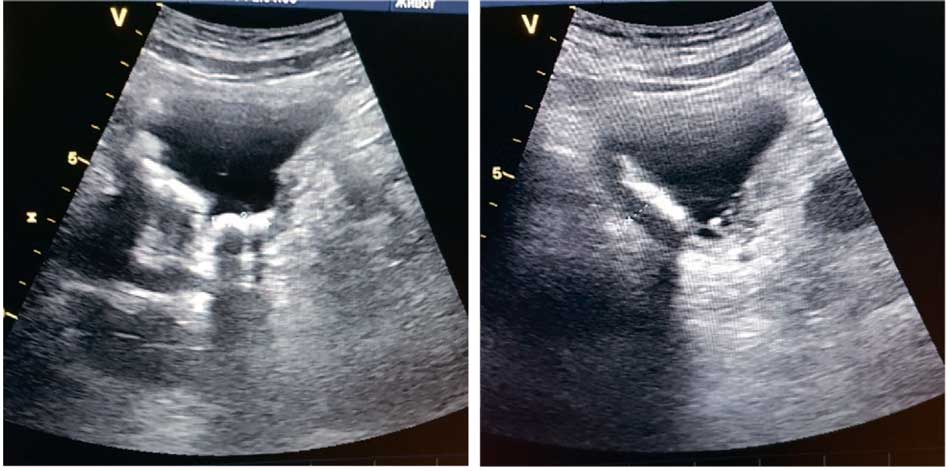

При оценке результатов УЗИ у всех пациентов обеих групп выявлено патологическое утолщение стенки наполненного мочевого пузыря свыше 4 мм [21], гиперэхогенная слизистая мочевого пузыря за счет инкрустации, наличие гиперэхогенных фиксированных к стенке или подвижных образований с эхотенью (конкрементов) в мочевом пузыре (рис. 1).

Рис. 1. Ультразвуковая картина — гиперэхогенные образования в просвете мочевого пузыря

Fig. 1. Ultrasound pattern. Hyperechoic formations in the lumen of the bladder